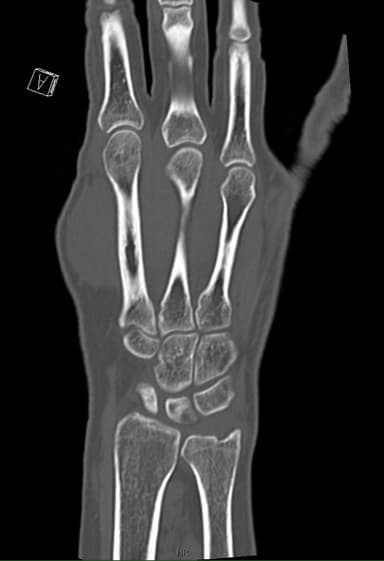

Frakturer, subtile kortikale skader, ledkongruens, knoglelæsioner og postoperativ vurdering.